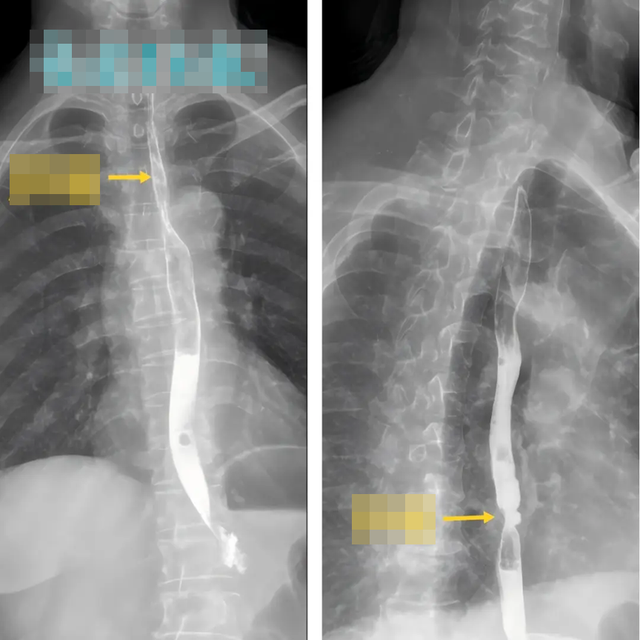

Sau khi đánh giá tình trạng bệnh, các bác sĩ đã chỉ định phẫu thuật nội soi trung thất để điều trị triệt căn ung thư thực quản cho cả hai bệnh nhân. Chỉ 5 ngày sau mổ, hai vợ chồng đã có thể xuất viện, sau khoảng một tuần phục hồi đã rút ống nuôi ăn và dần trở lại chế độ ăn bình thường.